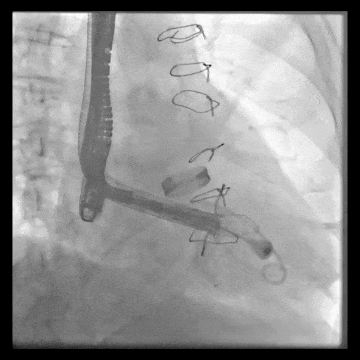

術(shù)中TEE觀察夾持件的位置

術(shù)后DSA

術(shù)后超聲評估瓣膜穩(wěn)定性良好,無瓣周漏